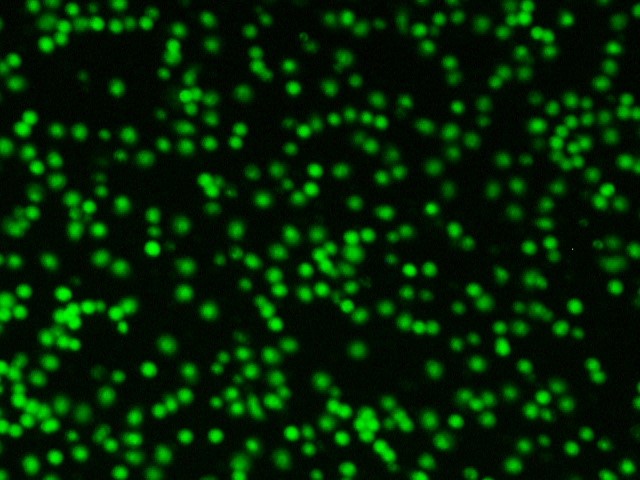

После введения цитопротекторов в лунки с лейкоцитарной взвесью пациентов с ИБС в «терапевтической концентрации» обнаружили два варианта изменения индекса жизнеспособности – в виде его повышения либо снижения, что зависело от исходных показателей анализа крови больных. О цитопротекторном эффекте препарата судили исключительно в случае повышения индекса жизнеспособности, т. е. при увеличении количества живых клеток и уменьшении количества мёртвых клеток в полях зрения (рисунок 3).

А1. Живые клетки в исходном состоянии | А2. Живые клетки после введения |

Fig. 3. Cytoprotective effect of the drug (fluorescence microscopy, 200× magnification)

А1 и А2 – увеличение количества живых клеток в поле зрения после введения цитопротекторного препарата (триметазидина или этоксидола) (окраска Сalcein АМ);

Б1 и Б2 – уменьшение количества мёртвых клеток в поле зрения после введения цитопротекторного препарата (триметазидина или этоксидола) (окраска Ethidium bromide).